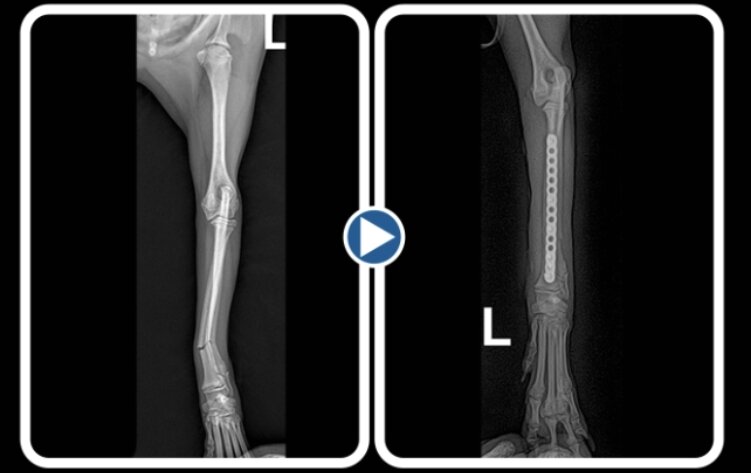

본문 이미지 - 플레이트를 이용한 반려견 요척골 골절 수술 방사선 사진(로얄동물메디컬센터 제고) ⓒ 뉴스1

플레이트를 이용한 반려견 요척골 골절 수술 방사선 사진(로얄동물메디컬센터 제고) ⓒ 뉴스1